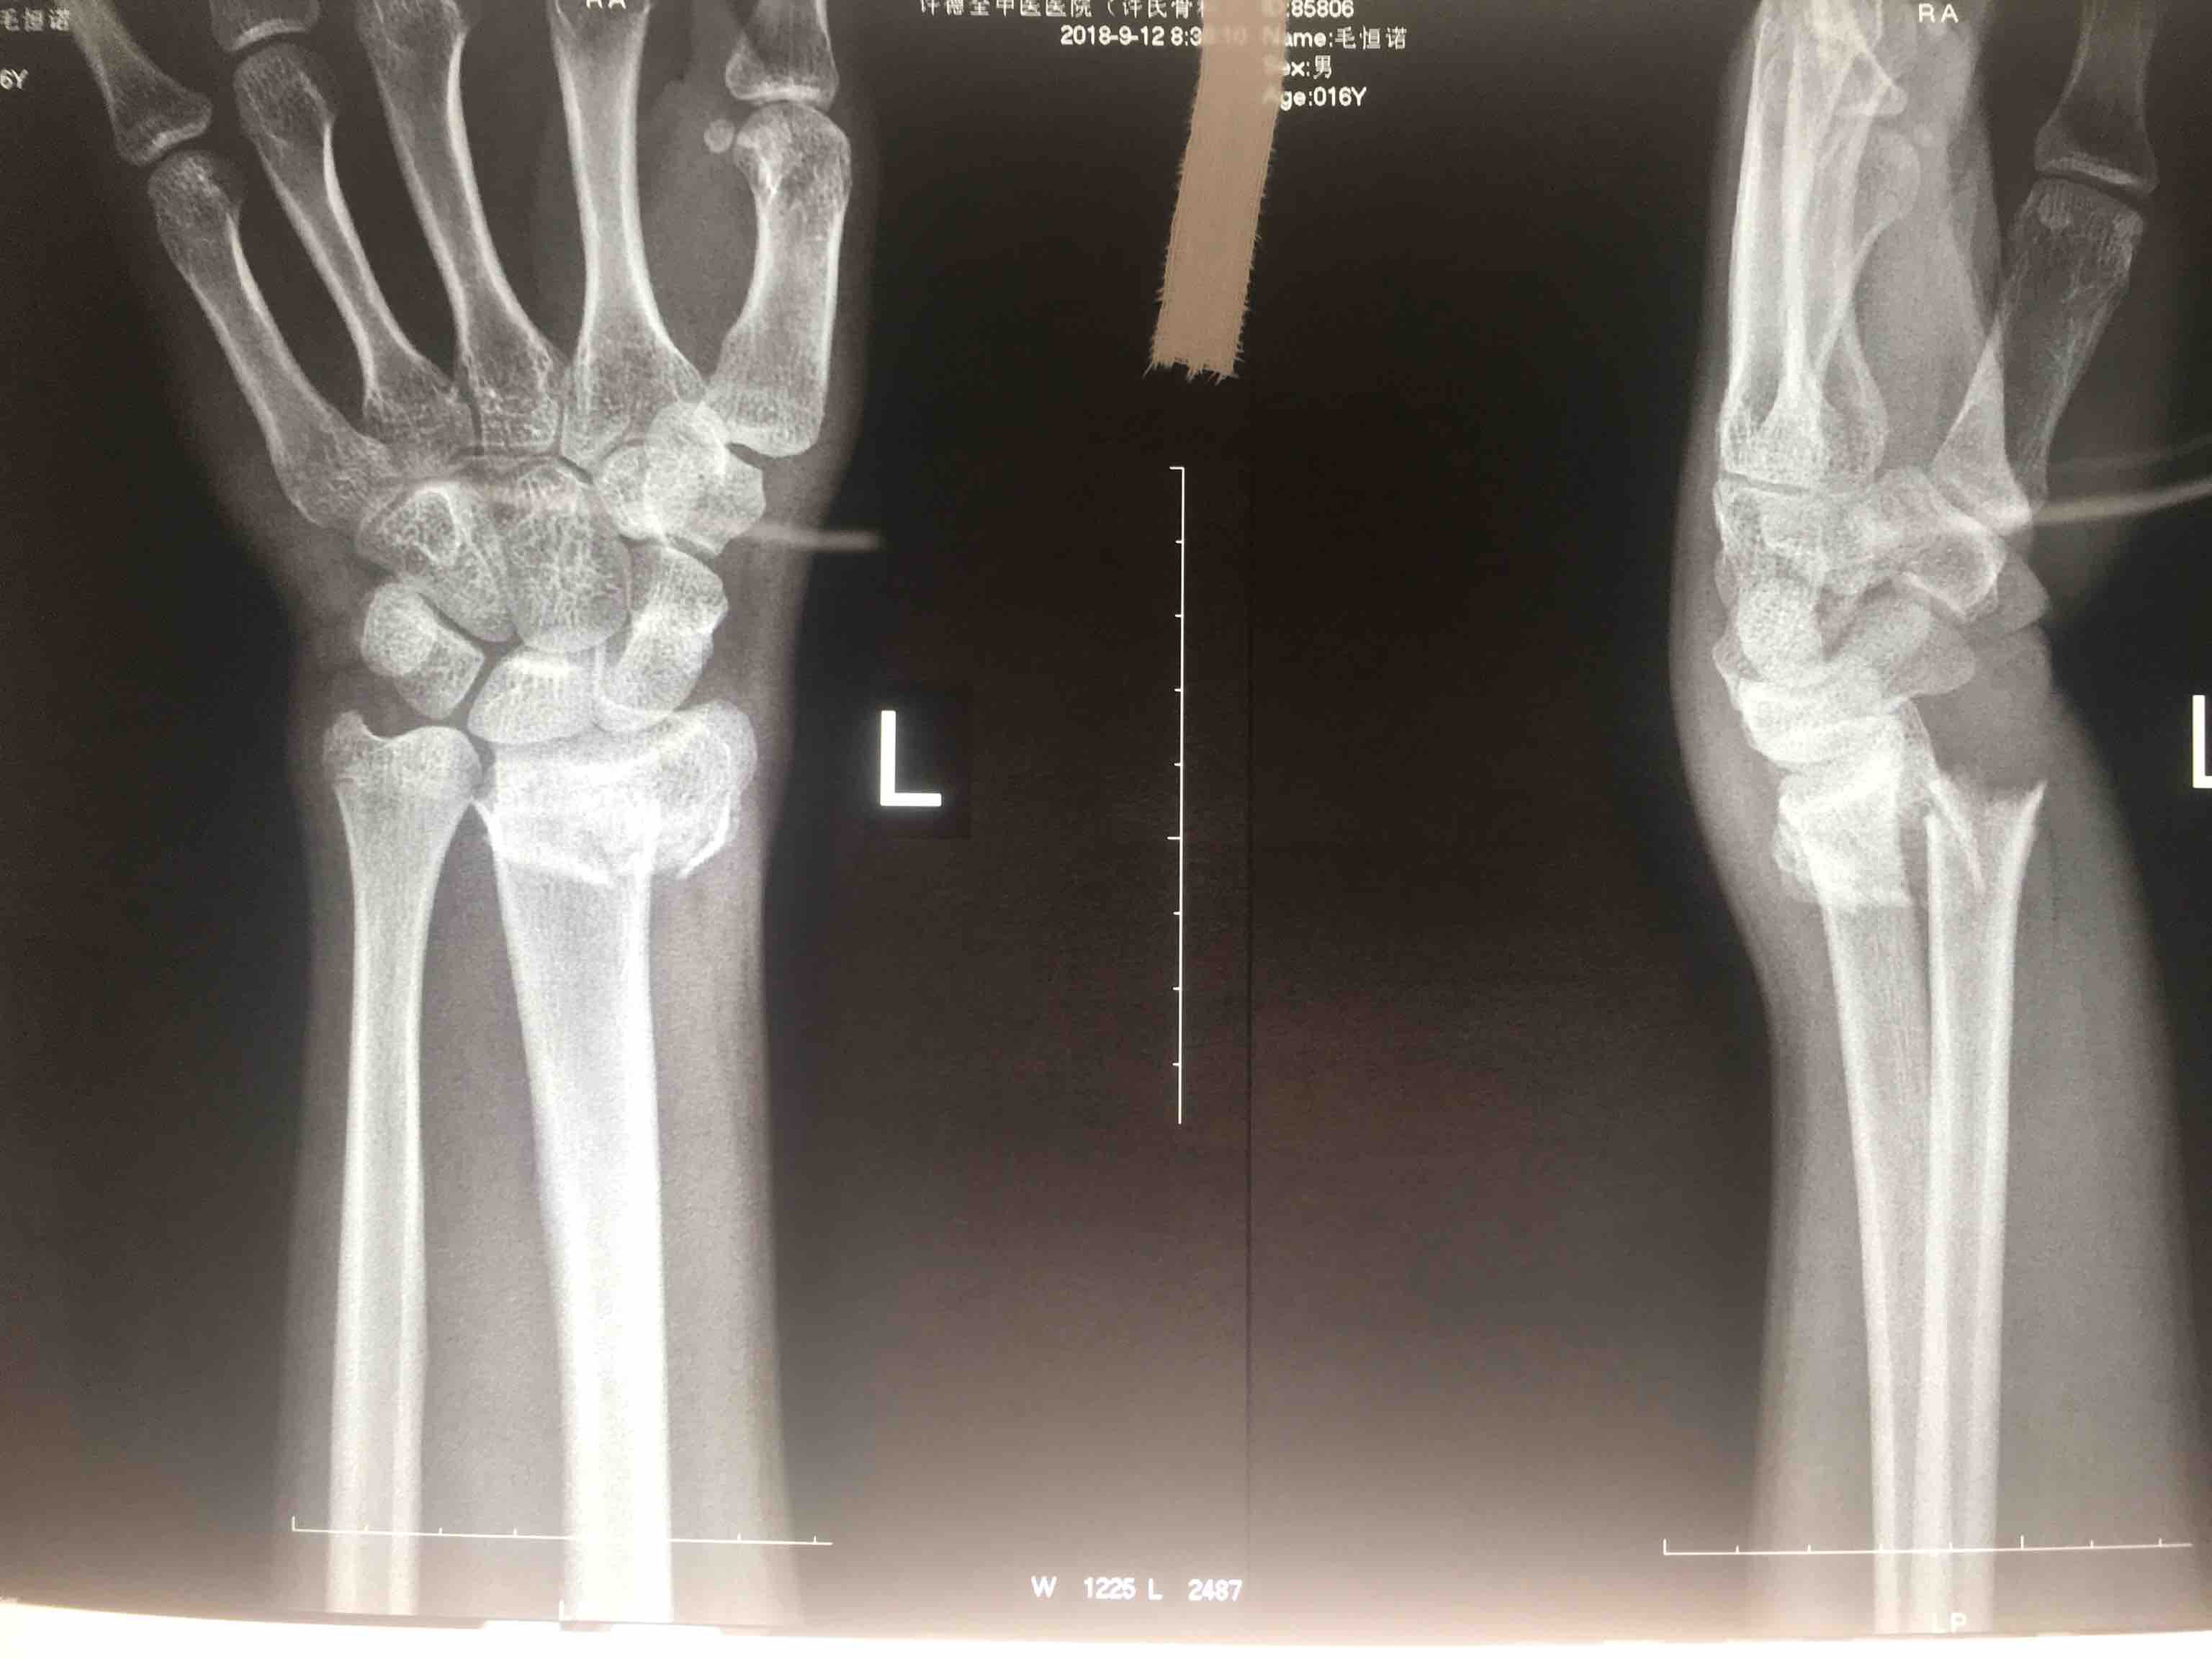

生命体征平稳,心肺复未见异常。左腕部肿胀明显,局部皮色皮温正常,畸形,压痛及纵向叩击痛阳性,腕关节活动受限,感觉血运正常。

诊断左colles骨折

儿童Colles骨折(切复内固定)

2018-09-12阅读量:1478